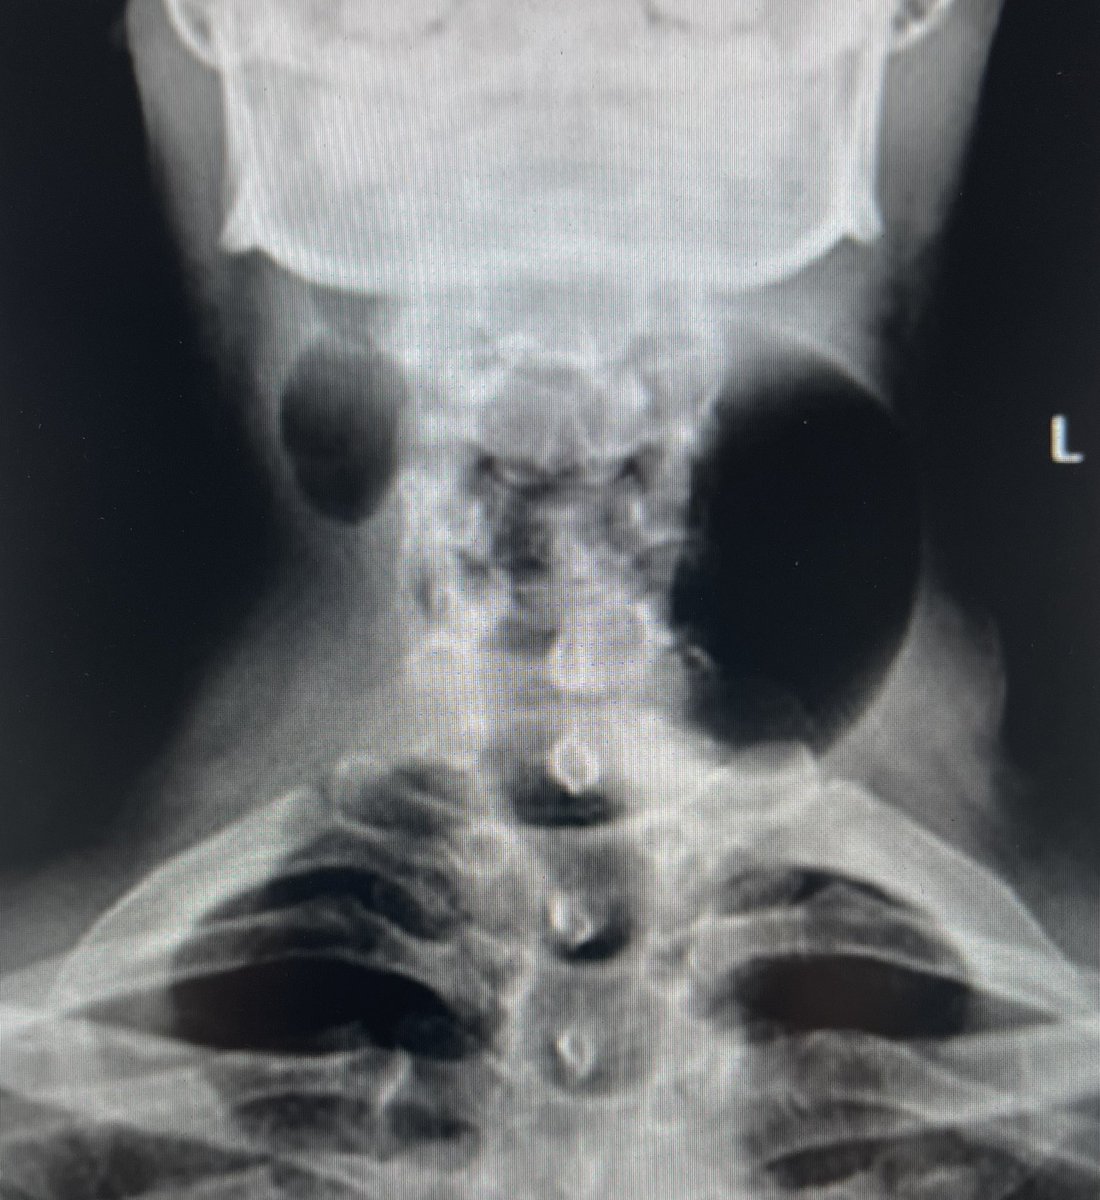

“Intermittent bilateral neck swelling.”

#HNrad

@SalmanQureshiDr

@RamVaidhyanath

@CMGlastonbury

@DShatzkes

@rhwiggins

@mattdbull

@iasepulveda

@stuart_viner

@BshniTrainees

Let’s see your GIF game strength…

Answer and clinical pic to follow…